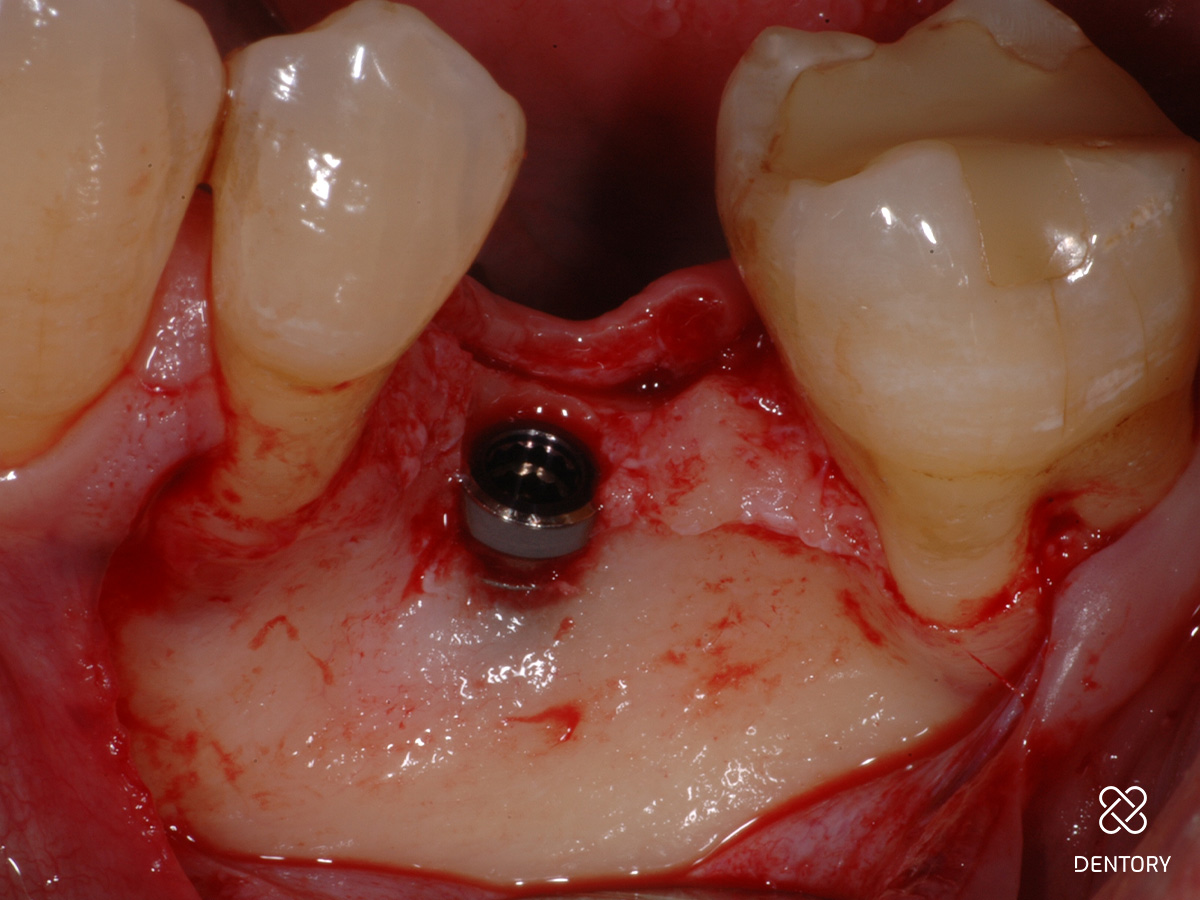

Abbildung 3

Okklusale Ansicht nach Insertion eines 4 mm-Implantats mit Plattform-Switching. Eine simultane Defektrekonstruktion erscheint möglich.

Abbildung 4

In der Lateralansicht zeigt sich ein moderater Dehiszenzdefekt bei gut erhaltener Knochenstruktur an den Nachbarzähnen, welche die Knochenregeneration unterstützen werden.